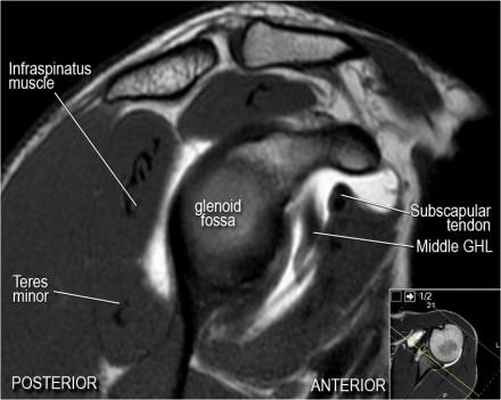

Изображение передних отделов плечевого сустава.

Сухожилие подлопаточной мышцы прикрепляется как к малому бугорку, так и к большому бугорку, давая поддержку длинной головке двуглавой мышцы в борозде двуглавой мышцы. Вывих длинной головки двуглавой мышцы плеча неизбежно приведет к разрыву части подлопаточной сухожилия. Манжета вращателей плеча состоит из сухожилий подлопаточной, надостной, подостная и малой круглой мышц.

Нормальная анатомия плечевого сустава в аксиальных изображениях и контрольный список.

- волокна сухожилия подлопаточной мышцы, создавая бицепитальную борозду, удерживают сухожилие длинной головки двуглавой мышцы. Изучите хрящи.

- уровень средней плече-лопаточной связки и передних отделов суставной губы. Поищите комплекс Буффорда. Изучите хрящи.